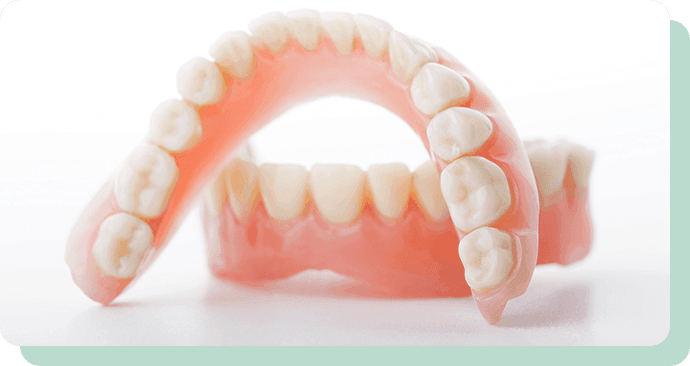

DENTURE

ぴったりフィットで、快適な食事を

歯を失った場合でも、入れ歯・義歯を装着することで噛むことや話すことなど、お口の機能を回復することができます。入れ歯・義歯には保険適用のものと適用外のものがあり、適用外(自費)のものは装着感や審美性で優位性があります。患者さまの症状やご希望により、適切な治療法を提案させていただきます。

参考模型